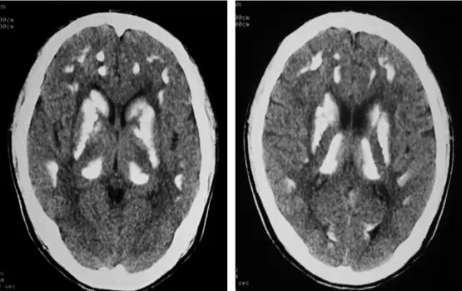

是因甲状旁腺分泌不足或先天性肾小管或骨对甲状旁腺反应不良而引起的疾病。本病发生多发对称性的脑内钙化,有一定特征性。

CT表现:主要表现为基底节或丘脑、脑叶、小脑齿状核区域多发对称性斑片状钙化。丘脑钙化表现为双侧类圆形,或尖向上的三角形。